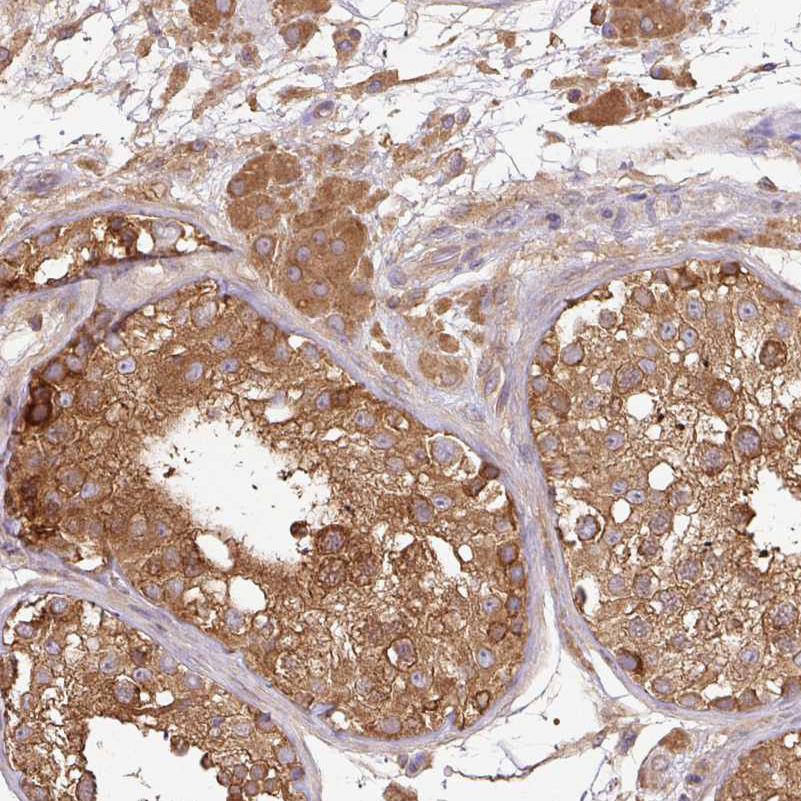

Immunohistochemical staining of human colorectal cancer shows moderate cytoplasmic positivity in tumor cells.